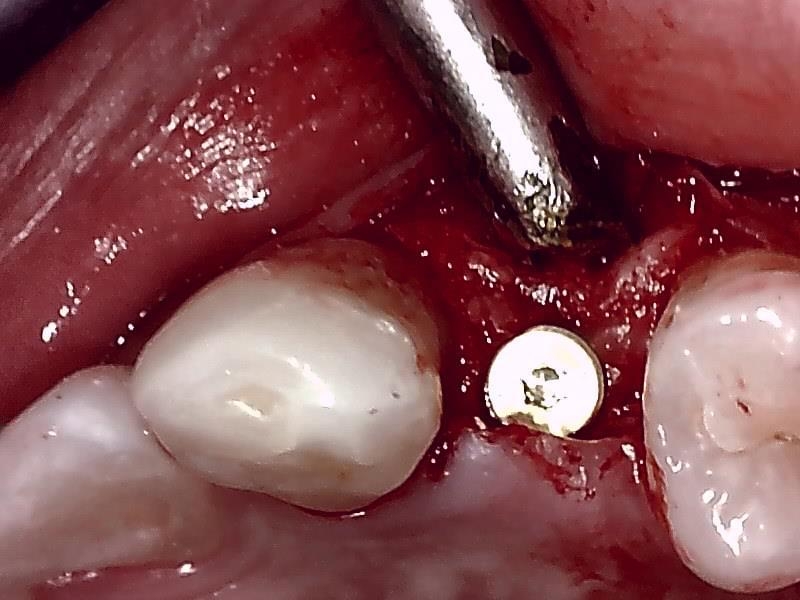

切開して歯肉剥離

ドリリング

インプラント体の埋入

ヒーリングアバットメント装着

骨造成 自家骨移植

縫合

術中インプラント埋入したあと、アバットメントの装着のため

顎堤部 歯槽骨にドリリングする。

インプラント体の口径に合わせて埋入孔を形成した状態です。